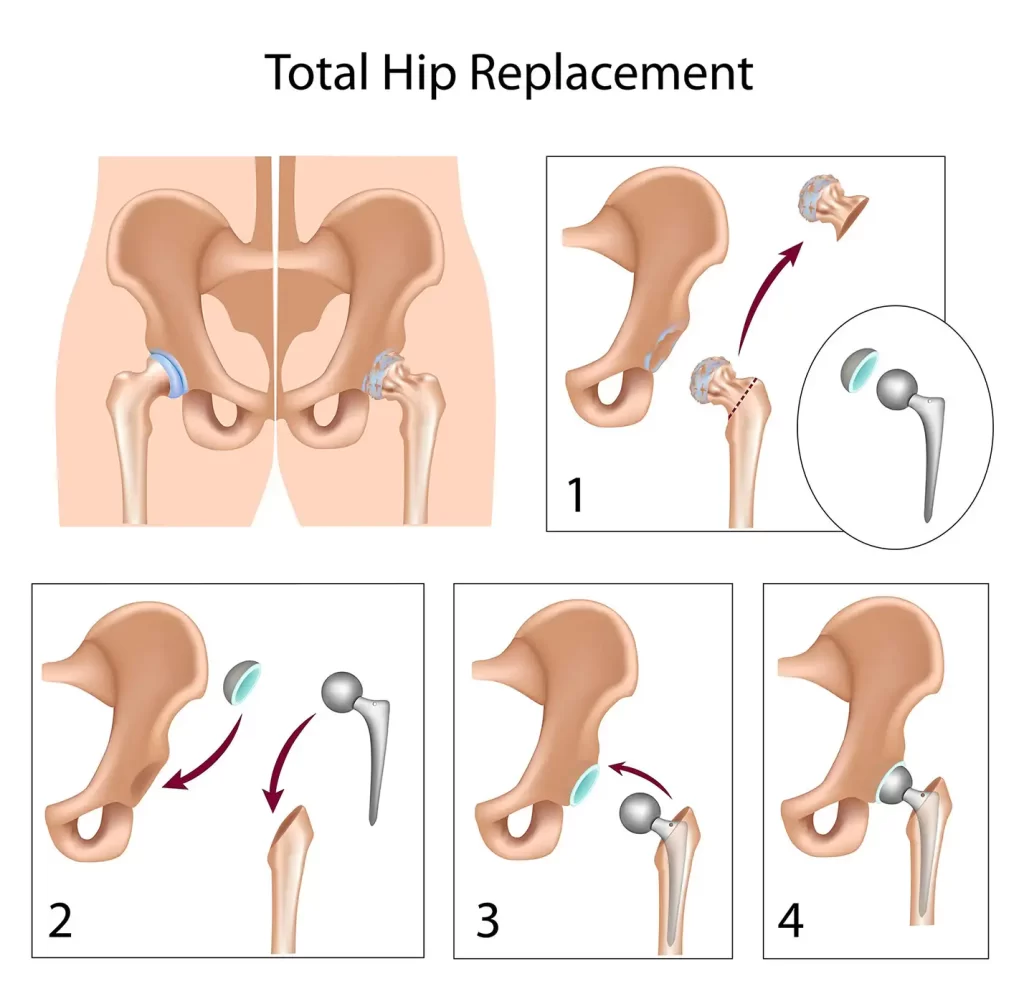

Below is a brief overview of how some of the more common geriatric fractures are managed, and what you can expect during these treatments.